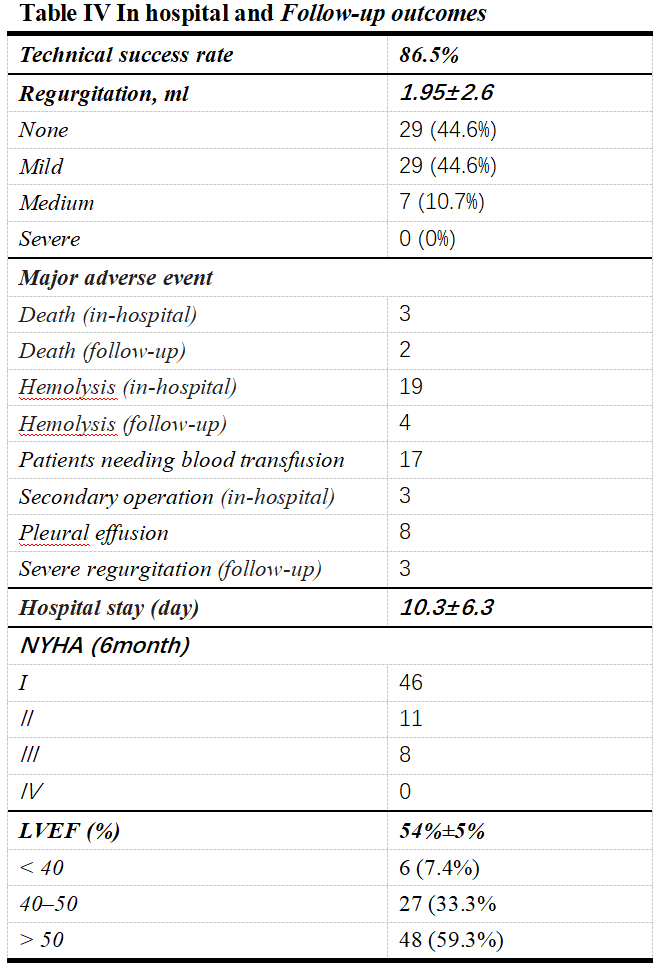

瓣周漏封堵术后,瓣周漏的返流量有显著的降低。NYHA分级及EF值均有较高的提升,术后并发症溶血值得关注,部分患者经输血治疗后改善。